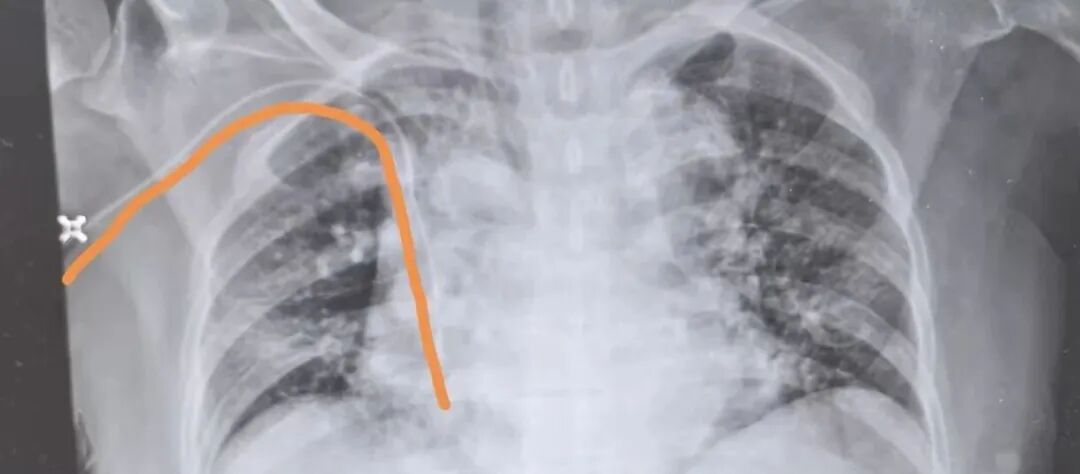

导管调整成功

“没想到第一次住院就遇到这么棘手的问题,还好有你们,让我们彻底放心了!”导管复位后,患者家属高兴地对护理团队说道。从初入院时的忐忑不安,到看着护理团队专业操作后的安心踏实,患者及家属的心态发生了彻底转变。